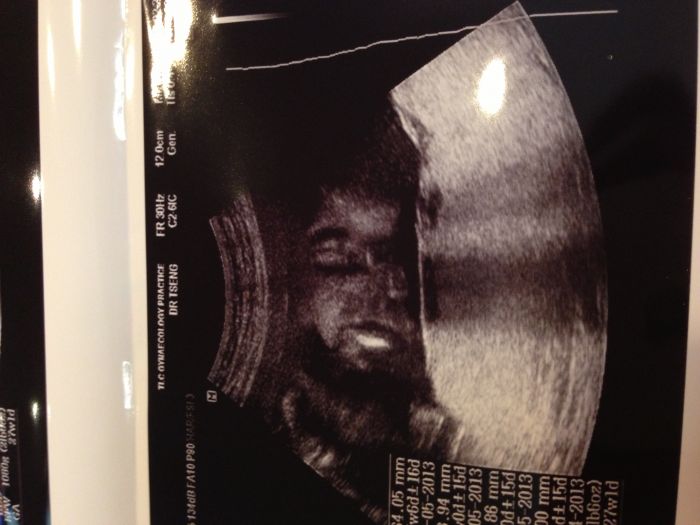

Ahoj holky taky se hlásím po delší odluce. Čtu vás ale nestíhám psát. Už za 4 dny letim do Austrálie, tak toho teď mám dost. Veru ty šaty bych řekla ok. Určitě to není nevhodné. :-) Moc ti to sluší. Ke kojeneckym podprsenkám- ja jsem si s dcerou koupila asi ve 30 týdnech a už mi byli super i po porodu a celou dobu kojení. Je pravda ze prsa se mi zvětšila asi týden po tom co jsem otehotněla, u obou děti, a u dcery i kdyz se mi na chvíli o trochu zvětšila po porodu, ta podprda se přizpůsobila. Byla bavlněná. Takže to asi záleží na kazdem. Jinak se musím pochlubit mojím úžasným ulovkem. Narazila jsem na bio pleny, látkové, takove ty kalhotkové a vyšli me jedny na $ 2 zlevněné ze 30. Úplne jsem nechapala. Tak jsem jich 5 koupila a k tomu všechny vložky které měli taky po 2 dolarech. To je asi 30kč za kus. Přidám fotečku. LeniK ty me desíš:-(. Ja po 11 letech mimo Čechy píšu jako tatar, a hlavně takhle z mobilu me to ten autokorekt upravuje a přivádí k šílenství. Tak se omlouvám:-( Jinak ja dnes poslední kontrola tady u doktora před odletem. A malej krasne zapózoval. První portrét. Otevíral pusu jako kdyz mluvi a klepal rukama. Dcera z toho byla úplne hotová. Říkala mami on na me mluvi:-) Dám vám sem fotku. Tak se opatrujte. Opatrně na briška.